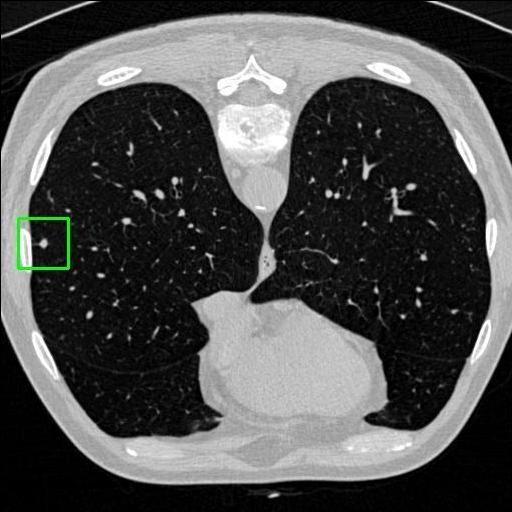

We developed an AI-based system using deep learning models for analyzing lung CT scans to detect and classify pulmonary nodules. We chose the YOLOv11 architecture for its enhanced object detection capability and adapted it specifically for medical imaging, incorporating pixel-level precision and severity classification.

Key Features: Real-time detection of nodules.

Classification into three severity levels with colored bounding boxes.

Maintaining performance on small, complex features like micro-nodules tested the limits of traditional object detectors.

Designed a severity classification system that categorizes nodules into null, moderate, and severe using colored bounding boxes, assisting in rapid clinical decision-making.